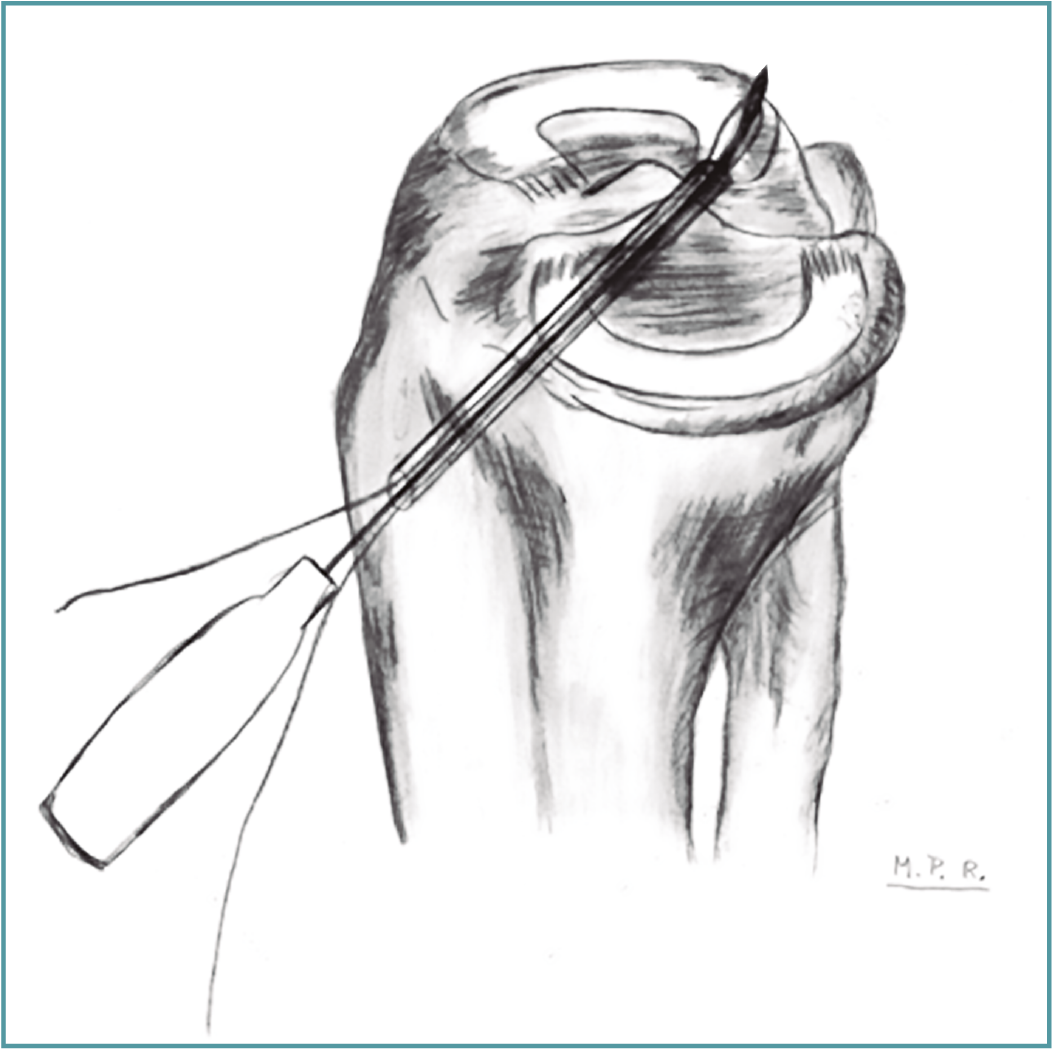

• Técnicas transtibiales: son las técnicas más utilizadas para la realización de la raíz posterior por su mayor facilidad de realización respecto a las técnicas in situ. Para su aplicación se realiza un túnel transóseo desde la cortical tibial anterior hasta la zona de inserción anatómica de la raíz en cuestión con la ayuda de una guía de LCA (Figura 8) desde una incisión accesoria anteromedial o anterolateral (en función del menisco afectado se utiliza una u otra, desde el lado contralateral para seguir la dirección de las fibras de inserción de la raíz intervenida); en caso de reconstrucción asociada de LCA, se puede utilizar la misma incisión anteromedial; algunos autores incluso proponen la utilización del mismo túnel para la reconstrucción del LCA y de la raíz meniscal(68). Los hilos con los que se realiza la sutura meniscal se introducen a través del túnel tibial para realizar la fijación dentro del túnel(68) y/o en la cara anterior de la tibia, mediante puente óseo (realizando doble túnel)(69), con un botón(11), con un implante sin hilos(12) o a un poste(70).

Figura 11. Esquema de la técnica de reinserción transósea de la raíz posterior del menisco lateral con el pasador de sutura a través del túnel tibial. La punta del dispositivo está perforando la raíz meniscal. Reproducido con permiso de Espejo-Baena A, et al. Arthrosc Tech. 2017 May 22;6(3):e621-e626(12).